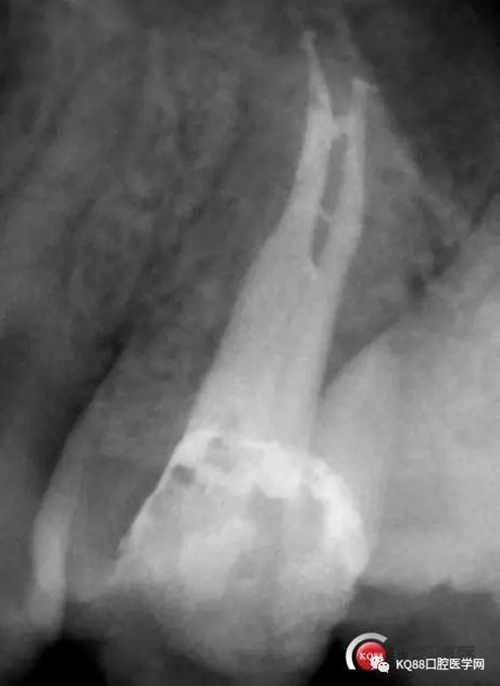

此次明顯可以看見(jiàn)根尖分開(kāi)了兩個(gè)根尖孔,根管治療永遠(yuǎn)就只是那一點(diǎn),如果都只是隨便做一下,我相信,沒(méi)有復(fù)雜的牙齒,根管治療都會(huì)很簡(jiǎn)單,態(tài)度決定一切,我不敢說(shuō)我做的會(huì)很好,但是我會(huì)靜下心來(lái),慢慢操作,這樣才能做得對(duì)的起自己和患者。于是根充完成,再次拍攝。

Y形態(tài)變形成了,根間支也明顯出現(xiàn),充填嚴(yán)密,雖然根管治療的成功率不是一百,但是我們盡可能把那一點(diǎn)做到位,往往結(jié)果可能會(huì)很驚人,如果我在第一次就充填了,可能也不會(huì)有什么錯(cuò)誤,但是態(tài)度就已經(jīng)輸了,我們基層做根管不會(huì)像武大等那么規(guī)范,但是也希望可以向其靠攏,一個(gè)好的根管,上面才能有美的修復(fù)。